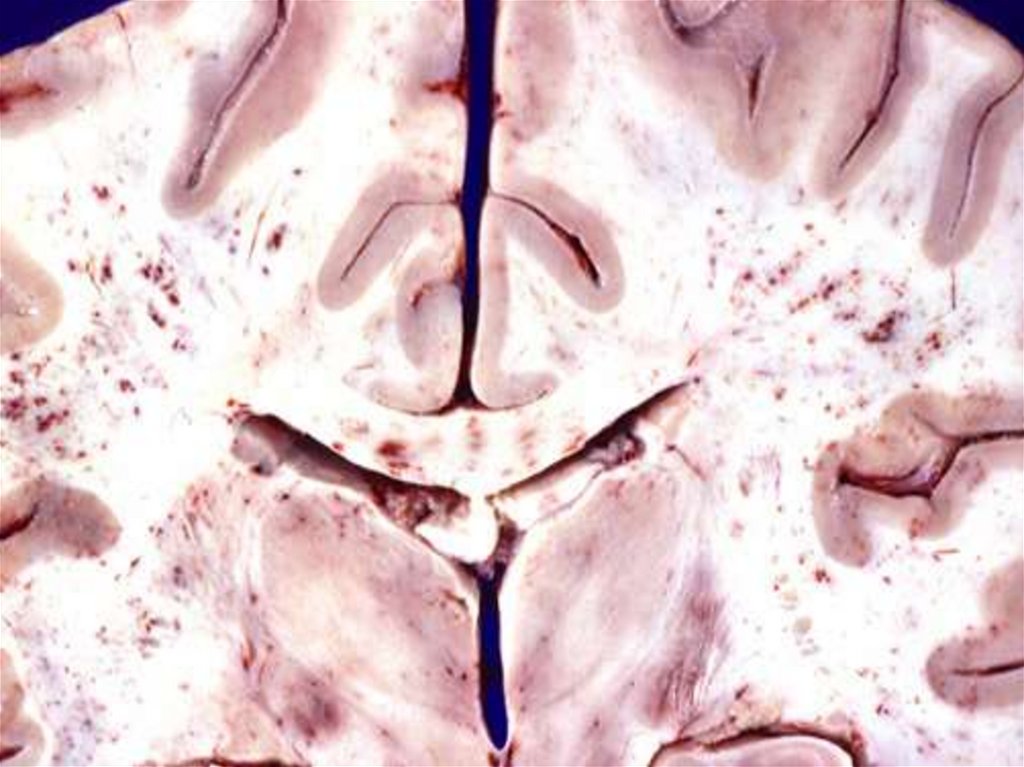

43. Кровоизлияние в головной мозг

7. Эмболия инородными телами